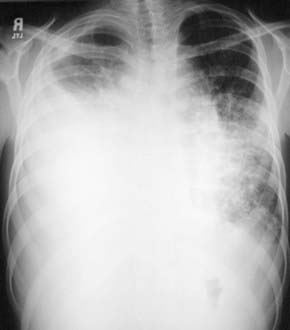

image

Figure 409-4 Spontaneous chylothorax in a 4 yr old with a duplication of chromosome 6. A, Chest radiograph shows opacification of the right thorax. B, CT scan shows the chylous pleural effusion (asterisk) compressing the atelectatic right lung (arrows).